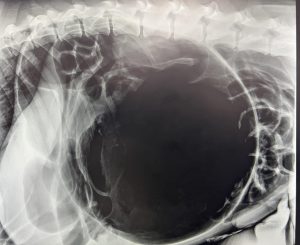

a Bernese Mountain Dog who was brought to us after his owners noticed he was becoming seriously unwell. The X-ray shows a GDV (Gastric Dilatation and Volvulus), where the stomach becomes dangerously enlarged with gas and twists on itself, blocking the normal passage in and out of the stomach. This is a life-threatening emergency.

Rancho was taken straight into emergency surgery for a suspected GDV (Gastric Dilatation and Volvulus). Following extensive surgery, Rancho recovered well and was able to return home, where he continues his recovery.